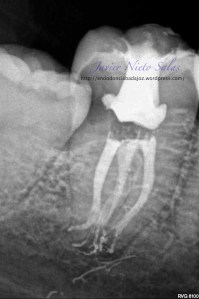

Se le volvió a citar a la paciente al mes, para reevaluar el caso.

Desaparece el sondaje patológico y la fistula.